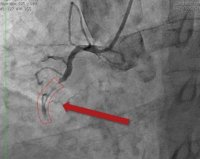

• Коронарная ангиография. Рентгеновская инвазивная коронарная артерия является основным методом проверки тромбоза стента. Коронарная ангиография выявляет дефект в одном из коронарных сосудов и отсутствие дальнейшего кровотока в этом месте. Часто встречается многососудистая коронарная окклюзия.